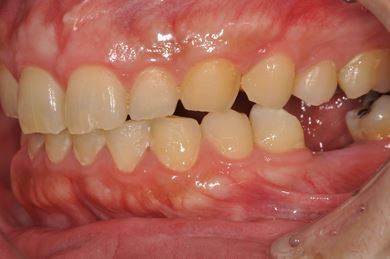

インプラントの症例写真 IMPLANT

インプラント治療+セラミック治療

| 性別/年齢 | 男性 / 32歳 | ||||||||||||||||||||||||||||||||

| 主訴 | 何ヵ所か虫歯が進行してしまったので治療をして欲しい。以前抜歯をした所についてはインプラントを希望する。 | ||||||||||||||||||||||||||||||||

| 治療内容 | インプラント1本、ハイブリッドセラミック4本、ハイブリッドセラミックインレー1本、歯肉歯槽骨整形 | ||||||||||||||||||||||||||||||||

| 総治療費 | 756,525円 | ||||||||||||||||||||||||||||||||

| 治療期間 | 8ヶ月 |